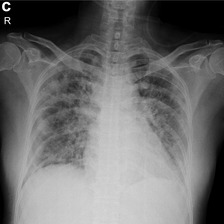

Across the world's coronavirus disease 2019 (COVID-19) hot spots, the need to streamline patient diagnosis and management has become more pressing than ever. As one of the main imaging tools, chest X-rays (CXRs) are common, fast, non-invasive, relatively cheap, and potentially bedside to monitor the progression of the disease. This paper describes the first public COVID-19 image data collection as well as a preliminary exploration of possible use cases for the data. This dataset currently contains hundreds of frontal view X-rays and is the largest public resource for COVID-19 image and prognostic data, making it a necessary resource to develop and evaluate tools to aid in the treatment of COVID-19. It was manually aggregated from publication figures as well as various web based repositories into a machine learning (ML) friendly format with accompanying dataloader code. We collected frontal and lateral view imagery and metadata such as the time since first symptoms, intensive care unit (ICU) status, survival status, intubation status, or hospital location. We present multiple possible use cases for the data such as predicting the need for the ICU, predicting patient survival, and understanding a patient's trajectory during treatment. Data can be accessed here: https://github.com/ieee8023/covid-chestxray-dataset